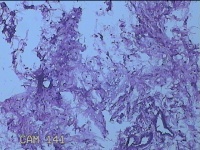

性别

女

年龄

36岁

临床诊断

皮肤良性肿瘤

发现左侧大腿息肉组织2年余,无明显疼痛及不适。

左侧大腿息肉组织

大体所见

灰白粉红色息肉样组织4.3x3.3x0.8cm一块,表面光滑,切开组织呈实性,切面灰白粉红色,质软。

图4